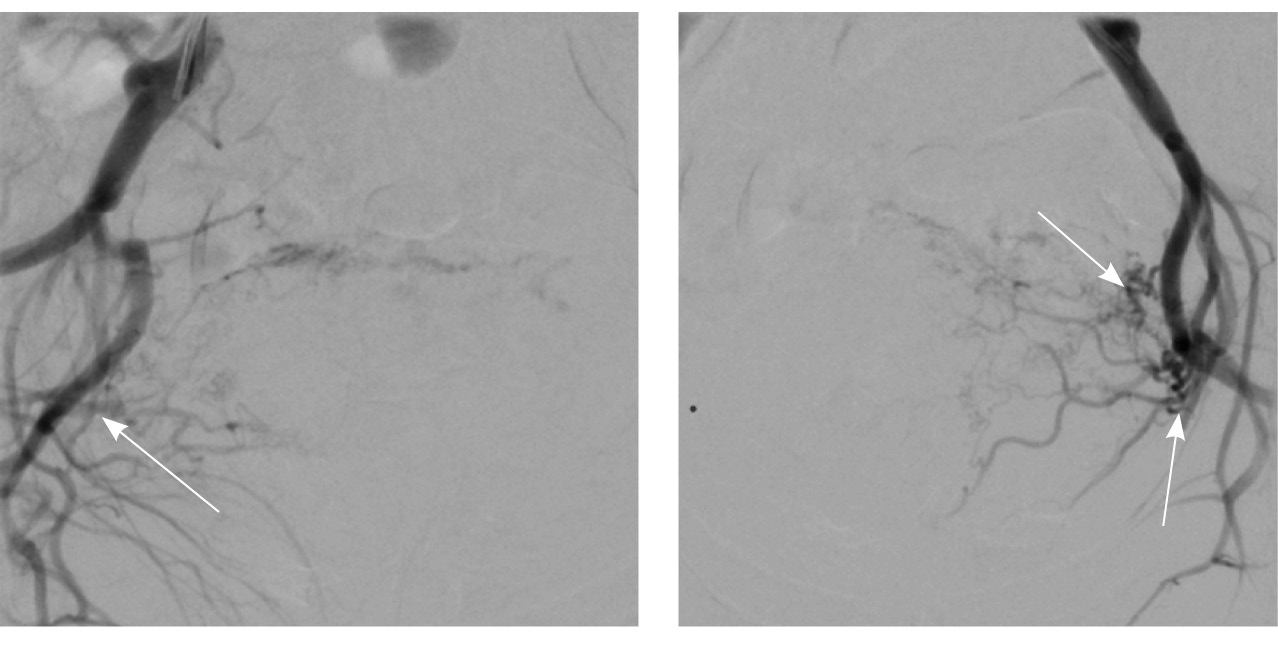

Пациентке выполнено МРТ-исследование на МР-томографе Siemens MAGNETOM Verio с индукцией магнитного поля 3T, с использованием стандартных катушек, в режимах Т1-взвешенного изображения (ВИ), Т2-ВИ, Т2-FS, FIESTA, DWI с получением изображений в сагиттальной, корональной и аксиальной плоскостях, динамическое внутривенное контрастирование (гадопентетовая кислота 0,2 мл/кг массы тела). Матка увеличена в размерах, с признаками снижения зональной дифференциации стенок, усиленным сосудистым компонентом, полость матки расширена с наличием примеси геморрагического содержимого, неравномерным утолщением эндометрия и пристеночными компонентами слизистой. В нижнем маточном сегменте определяется несостоятельный рубец от кесарева сечения, с наличием участка резко истонченной пролабирующей стенки матки слева и наличием дополнительного образования неоднородного сигнала, суммарно до 4,0 × 2,3 × 3,2 см, представленного фрагментами мягкотканного хориона (изоинтенсивного на Т2-ВИ), достигающего серозного покрова матки, и патологического сосудистого компонента в виде расширенных полнокровных сосудов, зон неоангиогенеза (рис. 1). На DWI признаков ограничения диффузии не определялось.

Рис. 1. Остатки вросшего хориона в несостоятельный рубец от кесарева сечения. Магнитно-резонансная томограмма, Т2-взвешенное изображение в сагиттальной (А), корональной (Б), аксиальной (В) плоскостях. Признаки наличия в проекции несостоятельного рубца от кесарева сечения фрагментов ткани вросшего хориона изоинтенсивного сигнала (отмечен звездочкой), с распространением до серозного покрова матки. Стрелками указаны гипоинтенсивные сосуды, зоны неоангиогенеза, артериовенозные сосудистые коллатерали